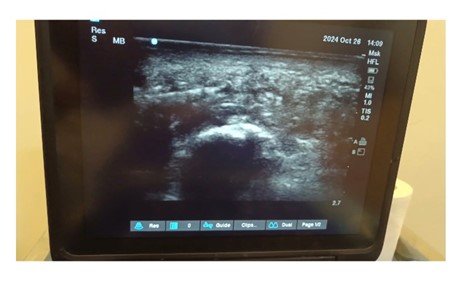

Benefits of Ultrasound Guidance

- Accuracy: Ultrasound imaging ensures the PRP is injected into the exact site of damage in the plantar fascia, avoiding unnecessary tissue injury.

- Real-Time Visualization: The clinician can monitor needle placement and tissue response in real time.

- Minimized Risk: Ultrasound guidance reduces complications, such as inadvertent injection into surrounding nerves or tissues.

- Ultrasound Preparation: The plantar fascia is visualized using an ultrasound machine to identify the exact site of damage.

- An ultrasound device is used to visualize the plantar fascia and surrounding structures.

- The inflamed or damaged areas are identified in real-time.